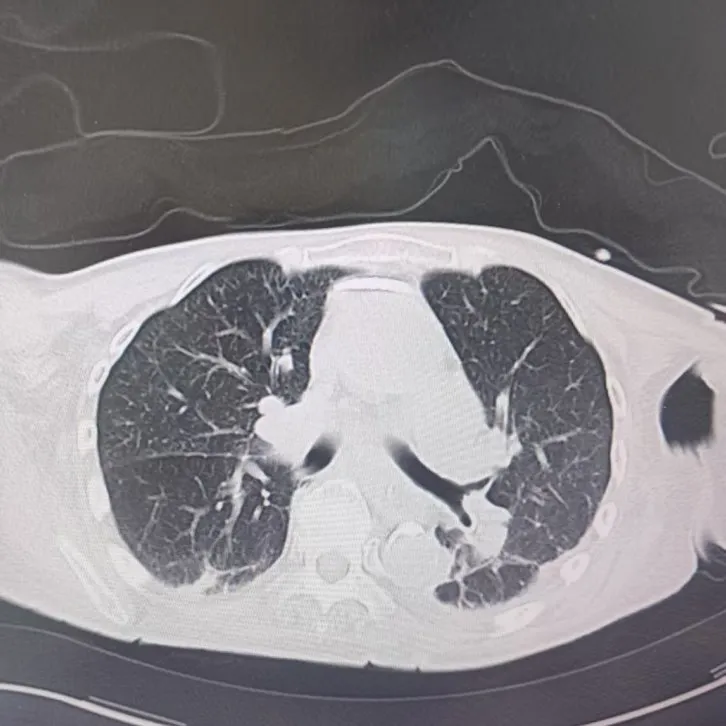

引言 / / Introduction 年近8旬的陈阿姨(化名)因脑梗长期瘫痪在床,康复期间突然高烧不退,体温升至39℃,在抗感染过程中,她并发高渗性脱水,病情急剧恶化,被紧急送入ICU。此时,她已气管切开,依靠呼吸机维持呼吸,并伴有低蛋白血症、低钾高钠血症及房颤等多种危重情况,命悬一线! PART. 01 多重泛耐药菌叠加大量基础病 治疗陷入“死胡同” 呼吸与危重症医学科及ICU通力协作,稳住患者生命体征。治疗过程中,进一步的病原学检查结果令人心惊:陈阿姨的肺部遭遇多种“超级细菌”混合侵袭,包括铜绿假单胞菌、鲍曼不动杆菌、嗜麦芽窄食单胞菌、金黄色葡萄球菌、木糖氧化无色杆菌、粘质沙雷菌等高度耐药菌,堪称耐药菌“大本营”。这些细菌对常用抗生素几乎全部耐药,治疗难度高,死亡率高。 治疗前患者肺部影像 PART. 02 多学科强强联手 量身定制攻坚方案 面对无药可用的困境,呼吸科没有放弃!宋刚主任带领团队联合药学部、检验科、重症医学科成立多学科治疗组,根据患者身体情况实时调整用药,逐一攻破耐药菌。这场与“超级细菌”的拉锯战持续了30多个日夜。 在医护日夜坚守和家属全力配合下,陈阿姨的感染终于被遏制:高烧退了,肺部阴影消散了!就在即将宣告胜利时,又发现她存在泌尿感染问题,随即转入泌尿外科协同治疗。当宋主任回访时,看到陈阿姨精神焕发、体温平稳,所有参与救治的人都感慨万分!这场救治,正是呼吸与危重症医学科攻坚耐药菌硬实力的生动体现! 治疗后患者肺部影像 从“无药可用”到“绝处逢生”,此次成功救治,集中体现了呼吸与危重症医学科以耐药菌精准诊治为核心的学科特色与技术优势。面对一次次的严峻挑战,科室始终秉持“生命至上、知难而进”的信念,以多学科协作为平台,凭借个体化精准用药策略,为患者寻找生机,为更多陷入困境的患者和家庭带去了实实在在的希望。 PART. 03 人民医院 人民名医 宋刚 主任医师 ·葫芦岛市第二人民医院呼吸与危重症医学科主任 ·辽宁省生命科学学会东北呼吸与危重症医学(PCCM)分会辽宁省基层委员会副主任委员 ·辽宁省细胞生物学学会放射粒子治疗专业委员会理事 ·辽宁省抗击新冠肺炎疫情先进个人 ·葫芦岛市劳动鉴定委员会专家库成员 ·葫芦岛市医学会呼吸内科学分会第三届委员会副主任委员 专业特色:擅长呼吸系统疑难及急危重患者的救治,如急慢性支气管炎、支气管哮喘、慢性阻塞性肺疾病、肺炎、肺栓塞、肺癌、间质性肺疾病、睡眠呼吸暂停综合征等,尤其擅长有创无创机械通气、支气管镜下相关检查及治疗(TBNA、气道支架置入术、球囊扩张等)、全肺灌洗术等领先技术,发表国家级期刊多篇。